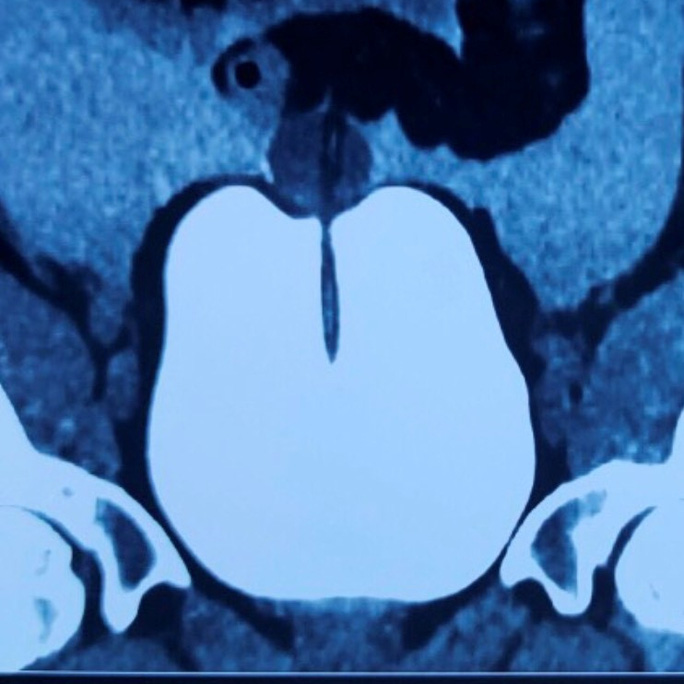

Bệnh viện Bạch Mai tối 21-12 cho biết Khoa ngoại bệnh viện này vừa tiếp nhận và điều trị một ca bệnh hy hữu và hiếm gặp trong y văn. Bệnh nhân là nam, 29 tuổi, bị vỡ bàng quang dẫn đến viêm phúc mạc sau một trận nhậu "tới bến" cùng bạn bè.

Theo hồ sơ bệnh án, sau cuộc nhậu cùng những người bạn, nam thanh niên này về nhà trong tình trạng "say mềm". Đến 2 giờ sáng, anh này muốn đi tiểu nhưng đau buốt và không thể đi nổi. Nam thanh niên cố chịu đến sáng để đi bệnh viện. Tại cơ sở y tế đầu tiên, bác sĩ đã thăm khám lâm sàng và thấy quá khả năng chuyên môn nên đã chuyển bệnh nhân đến Bệnh viện Bạch Mai.

Tại đây nam bệnh nhân nói trên được thăm khám lâm sàng và chỉ định làm các xét nghiệm, đánh giá cận lâm sàng với chẩn đoán vỡ bàng quang - viêm phúc mạc và được chỉ định phẫu thuật.

Bác sĩ Vương Xuân Thủy, Khoa Ngoại, Bệnh viện Bạch Mai - người trực tiếp tiến hành ca phẫu thuật cho bệnh nhân, cho biết bệnh nhân được phẫu thuật cấp cứu ngay sau đó, nhưng do đến bệnh viện muộn nên đã bị viêm phúc mạc. Kíp phẫu thuật đã hút được khoảng 2 lít dịch, nước tiểu trong khoang bụng và phẫu thuật tạo hình bàng quang. Hiện bệnh nhân đang được theo dõi, điều trị và dần hồi phục.

Chia sẻ về ca bệnh này, bác sĩ Thủy cho biết chấn thương lúc bàng quang căng đầy là chấn thương thường gặp ở những bệnh nhân uống nhiều rượu bia rồi bị té ngã hoặc bị tai nạn. Ngoài ra, còn có những trường hợp do trâu bò húc hoặc do tai nạn giao thông. "Với bàng quang căng đầy, thành bàng quang rất mỏng nên khi sức ép bên trong bị tăng cao đột ngột, hoặc khi có chấn thương rất dễ bị vỡ"- bác sĩ Thuỷ giải thích.

Bác sĩ Thủy cũng khuyến cáo mọi người tuyệt đối không nên nhịn tiểu. Khi có triệu chứng bất thường, nên đến cơ sở y tế sớm nhất để có những biện pháp hỗ trợ, điều trị kịp thời.